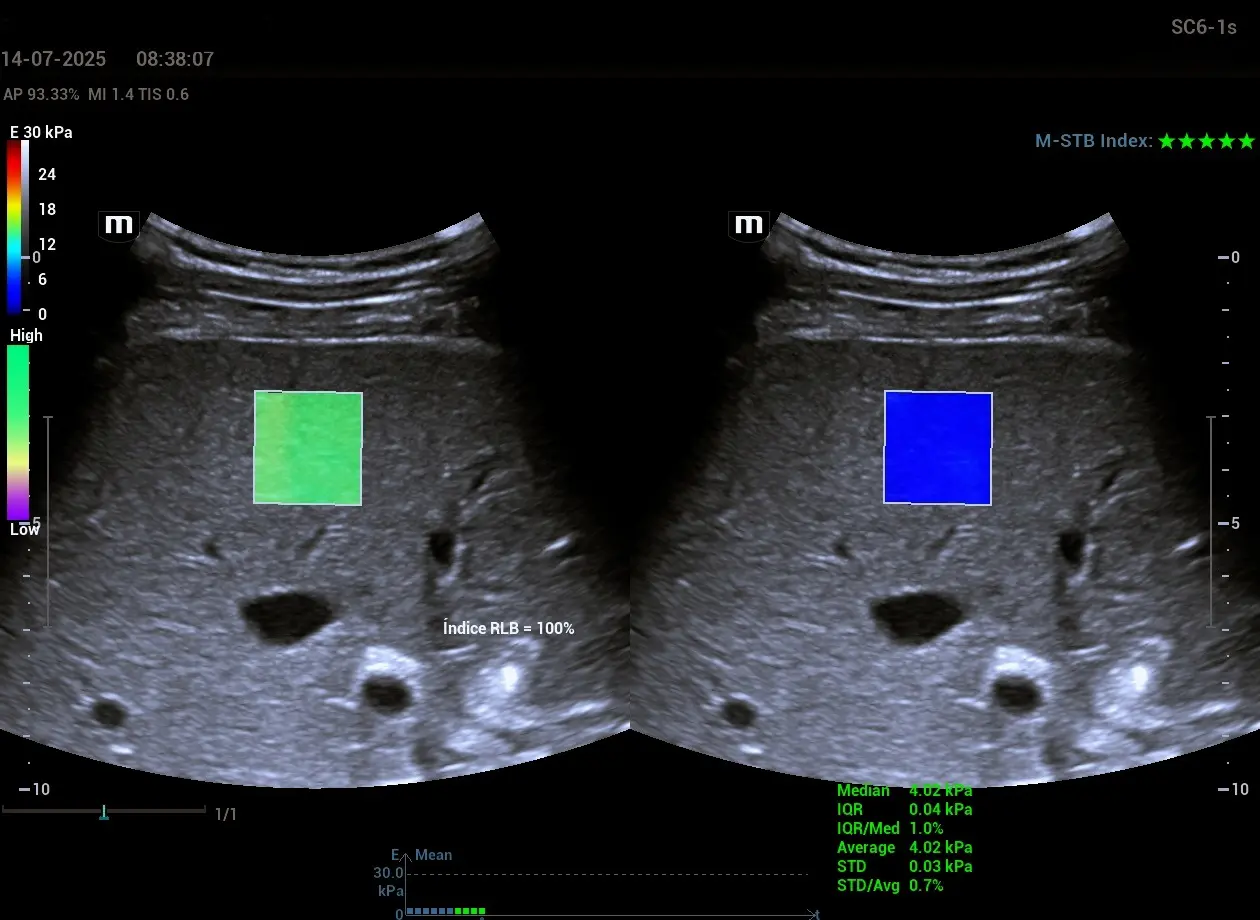

- Elastografía y ultrasonido de microvascularidad para evaluación de tejidos infantiles: estas técnicas permiten evaluar la elasticidad del hígado, riñón o tiroides, e incluso visualizar flujos vasculares de pequeño calibre en niños, complementando la ecografía convencional con información funcional y cuantificable. Esto amplía el espectro del diagnóstico temprano de fibrosis hepática, nefropatías o alteraciones tiroideas.